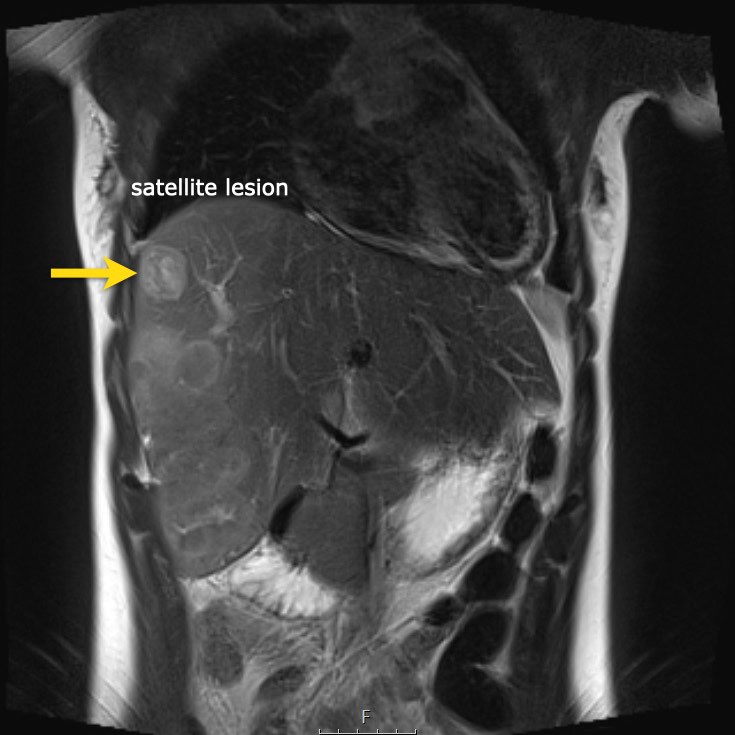

Ví dụ 1

Một bé gái 17 tuổi nhập viện với triệu chứng đau bụng vùng thượng vị. Siêu âm phát hiện một khối u gan lớn.

Trên MRI thấy khối u ở phân thùy gan 5 và 6 với các tổn thương vệ tinh ở phân thùy 7 và 8 (mũi tên). Có huyết khối u trong tĩnh mạch cửa phải (đầu mũi tên) và nhiều di căn phổi (*).